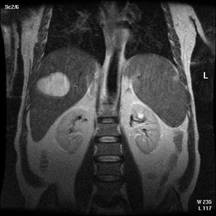

In stare de repaus, protonii de H din corpul omenesc sunt orientati anarhic. Daca ii supunem unui camp magnetic static intens care actioneaza din afara corpului la o temperatura joasa, ei se aliniaza cu axul lor paralel sau antiparalel cu directia campului magnetic. Sub actiunea unui alt camp exterior, protonii isi pierd orientarea si alinierea revenind la pozitia lor initiala de echilibru, trec printr-o faza de tangaj care consta intr-o miscare de rotatie analoga miscarii unui titirez in timpul careia emit un semnal de rezonanta receptionat de bobinele detectoare. Amplitudinea semnalului receptionat este proportionala cu numarul de nuclei din proba. Protonii de H care se vad mai bine sunt cei legati de apa si grasimi. Aceste doua medii dense in protoni apar albe, osul (15 % apa) apare negru ca si plamanul. Fluidele in miscare avand protonii in miscare au semnale foarte slabe.(jos-imagini rezonanta magnetica-abdomen, respectiv coloana cervicala)